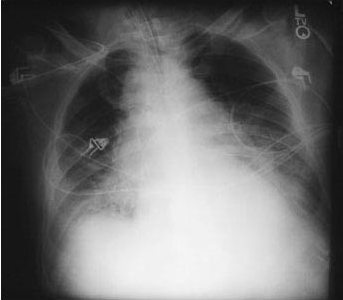

- Patients with inhalational anthrax infection present with malaise, myalgia, fever, cough, dyspnea, and substernal chest discomfort; radiographic imaging reveals a widened mediastinum resulting from hemorrhagic mediastinal lymphadenopathy.